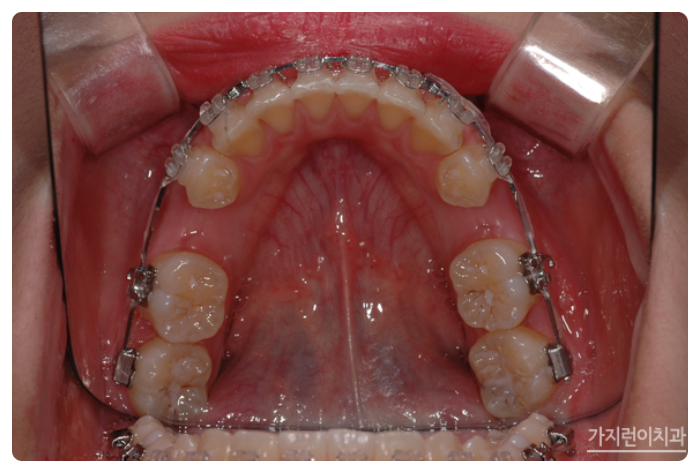

서울가지런이치과 교정과 의원, 강남에서도 거미스마일과 돌출입 치아교정이 이루어지고 있었는데요. 충분한 치아이동 공간을 확보하기 위해 상하악 1소구치를 발치한 후에 상악 잇몸뼈에 미니스크류를 식립해 효과적으로 힘을 주어 치아를 이동시켰습니다. 미니스크류를 진행하게 되면 상악 전치의 후방 이동이 일어나면서 상악 전치를 위로 합입시킬 수 있는데요. 상악이 어느 정도 이동한 것을 확인한 후에 하악에도 미니스크류를 식립해 상하악 전치를 동시에 후방으로 이동시킬 수 있었습니다.

약 1년 8개월 정도의 시간이 소요됐지만 환자분의 경우 거미스마일 교정과 더불어 돌출입 교정도 깨끗하게 진행이 되었는데요. 이처럼 교합면도 개선하고 돌출입과 잇몸이 많이 보이는 증상까지 개선해보니 안모 변화도 기대해볼 수 있었습니다.